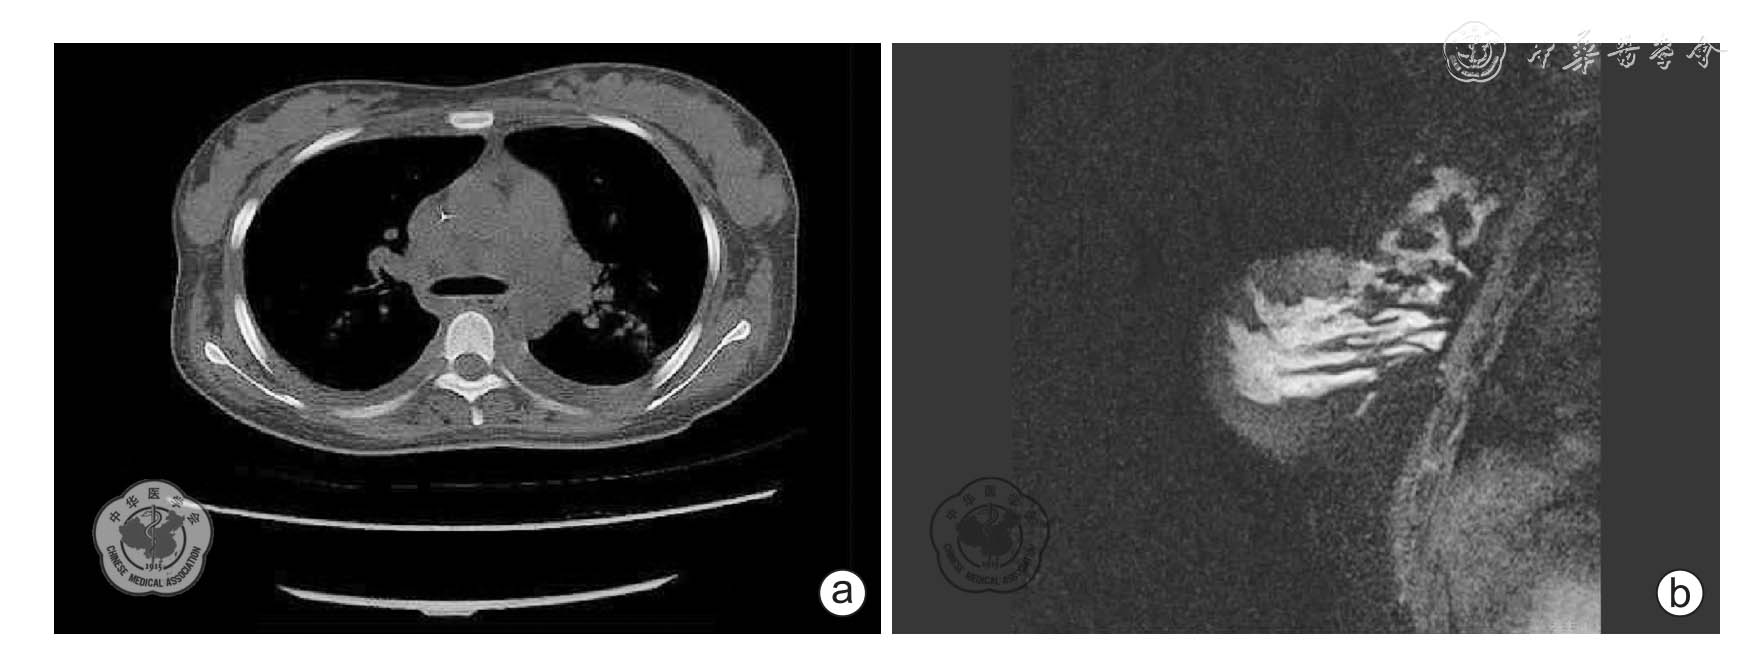

图1 乳腺粒细胞肉瘤影像学资料

a:病例1 的乳腺CT 图(双侧乳腺包块); b:病例2 的乳腺MRI 图(乳腺包块)

病例1,女,26 岁,已婚,因“乳腺包块3 个月,伴乏力2 周”于2012 年9 月23 日入院。 患者于2012 年6 月中旬(怀孕3 月)触及双侧乳腺数个包块,质地较硬,最大包块约鸡蛋大小,且入院前2 周出现乏力并加重,遂至本院就诊,门诊查血常规显示:WBC 17.34×109/L,Hb 91 g/L,PLT 57×109/L;外周血细胞形态:100 个细胞中见原始粒细胞62 个,早幼粒细胞14 个。 门诊以“急性白血病”收住本院。 入院查体:体温37.4 ℃,轻度贫血貌,浅表淋巴结未触及明显肿大,双侧乳房触及多个包块,最大包块为4 cm×5 cm,质硬,活动度差,无压痛;宫底位于脐上3 横指,胎心位于左下腹,162 次/分。 入院后骨髓细胞学检查显示:骨髓有核细胞增生明显活跃,粒、红细胞系增生抑制,单核细胞异常增生,原始及幼稚单核细胞占70%,此类细胞体积大,细胞质丰富,可见Auer 小体。 巨核细胞较易见,血小板少见。 骨髓白血病细胞免疫表型显示:CD15、CD34、CD117、CD33、CD64、人类白细胞抗原(HLA)-DR 均阳性,染色体核型46,XX[20/20]。 乳腺超声结果:腺体回声不均匀,见多个低回声包块布满双乳,界限清楚,形态规则,似有包膜,内部回声不均匀;左、右乳腺的最大包块分别为2.5 cm×1.8 cm、2.4 cm×1.9 cm。 胸部CT 显示(图1a):双侧乳房增大;腺体结构消失,见多发软组织团块状影,边界部分较清楚,部分弥漫生长边界不清;病灶呈等或略高密度。 乳腺包块粗针穿刺活组织病理检查(图2 a、b):粒细胞肉瘤,Lysozyme(++)、CD117(++)、髓过氧化物酶(myeloperoxidase,MPO)(++)、CD68(+)。 诊断:(1)急性髓系细胞白血病M5;(2)乳腺粒细胞肉瘤。 患者引产后给予多种方案化疗,其中有去甲氧柔红霉素+阿糖胞苷、脂质体多柔比星+阿糖胞苷等,并行乳腺局部放射治疗,均未缓解,确诊7 个月后终因白血病乳腺、肺、肝、脾多脏器浸润致全身衰竭死亡。